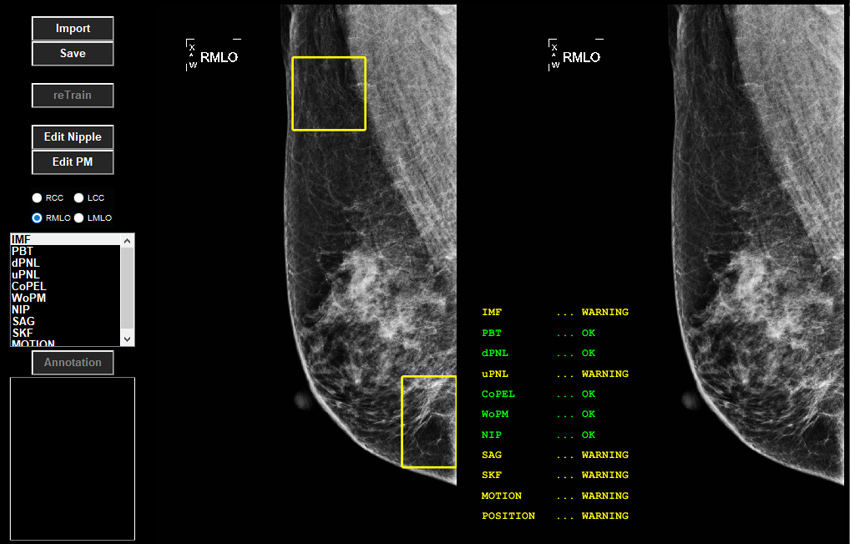

Mammography Quality Evaluation (MQE) uses 11 criteria of mammography quality that enhance radiographers’ skills and mammography process. Radiographers can adjust operations referring to MQE’s quality warnings and visual information. MQE helps hospitals to acquire quality mammograms and minimizes the chance of patient recall for retaking mammograms.